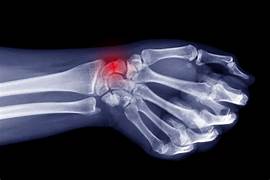

Frozen Shoulder, Gout Treatment